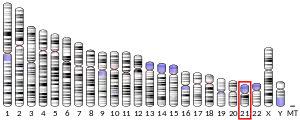

Genetics

Amyloid-beta precursor protein is an ancient and highly conserved protein.[11] In humans, the gene APP is located on chromosome 21 and contains 18 exons spanning 290 kilobases.[12][13] Several alternative splicing isoforms of APP have been observed in humans, ranging in length from 639 to 770 amino acids, with certain isoforms preferentially expressed in neurons; changes in the neuronal ratio of these isoforms have been associated with Alzheimer's disease.[14] Homologous proteins have been identified in other organisms such as Drosophila (fruit flies), C. elegans (roundworms),[15] and all mammals.[16] The amyloid beta region of the protein, located in the membrane-spanning domain, is not well conserved across species and has no obvious connection with APP's native-state biological functions.[16]